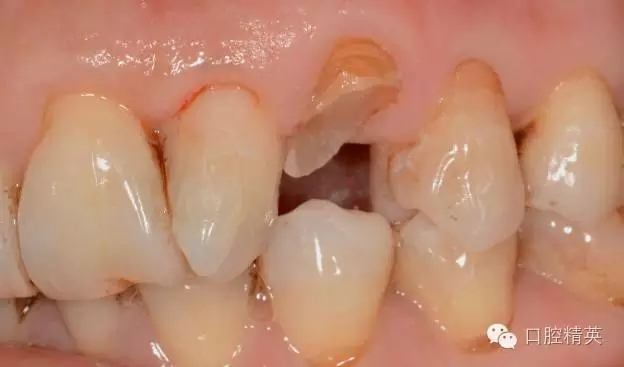

圖1 23口內(nèi)修復(fù)前情況:殘根位于齦上3MM,牙周無紅腫.